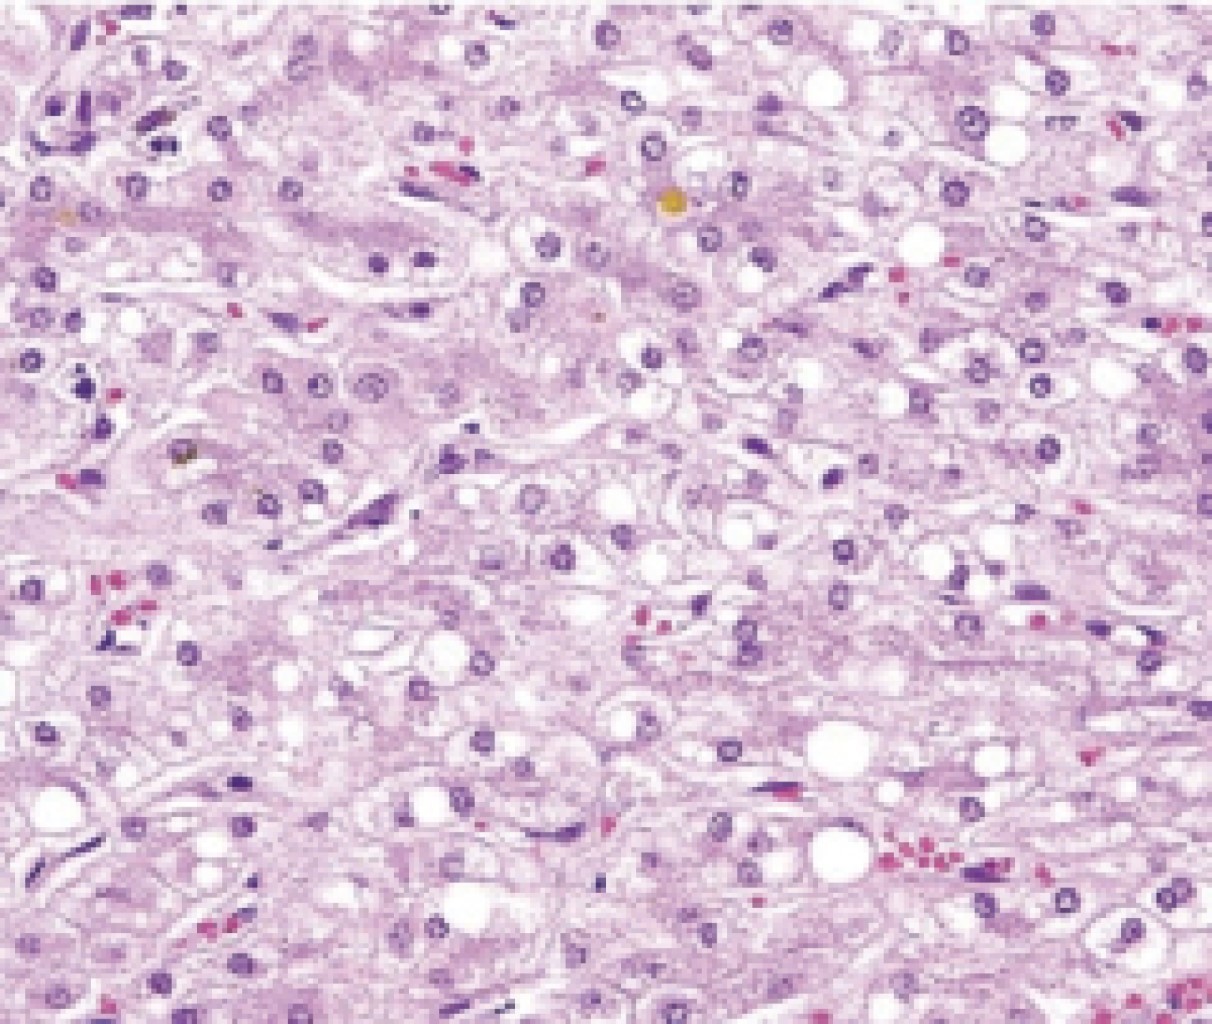

Transoperative bleeding was 800 ml. Postoperative pain management was performed with ketorolac at 30 mg IV c/8 hours, cefotaxime 1 g IV c/8 hours was used during the hospital stay, and the patient was discharged on the sixth postoperative day. The histologic report of the lesion was a well-differentiated hepatocarcinoma, grade 2, in the modified Edmondson-Steiner classification. It was encapsulated, measuring 7 × 5 × 4 cm, with regenerating nodules (Figure 4) and with tumor-free margins of 1 cm. The histopathologic report of the non-tumorous liver was non-alcoholic fatty liver grade 1 activity (30% steatosis, lobular focus of inflammation) and grade 2 fibrosis (portal fibrosis and pericellular fibers without fibrous bridges).

Figure 4